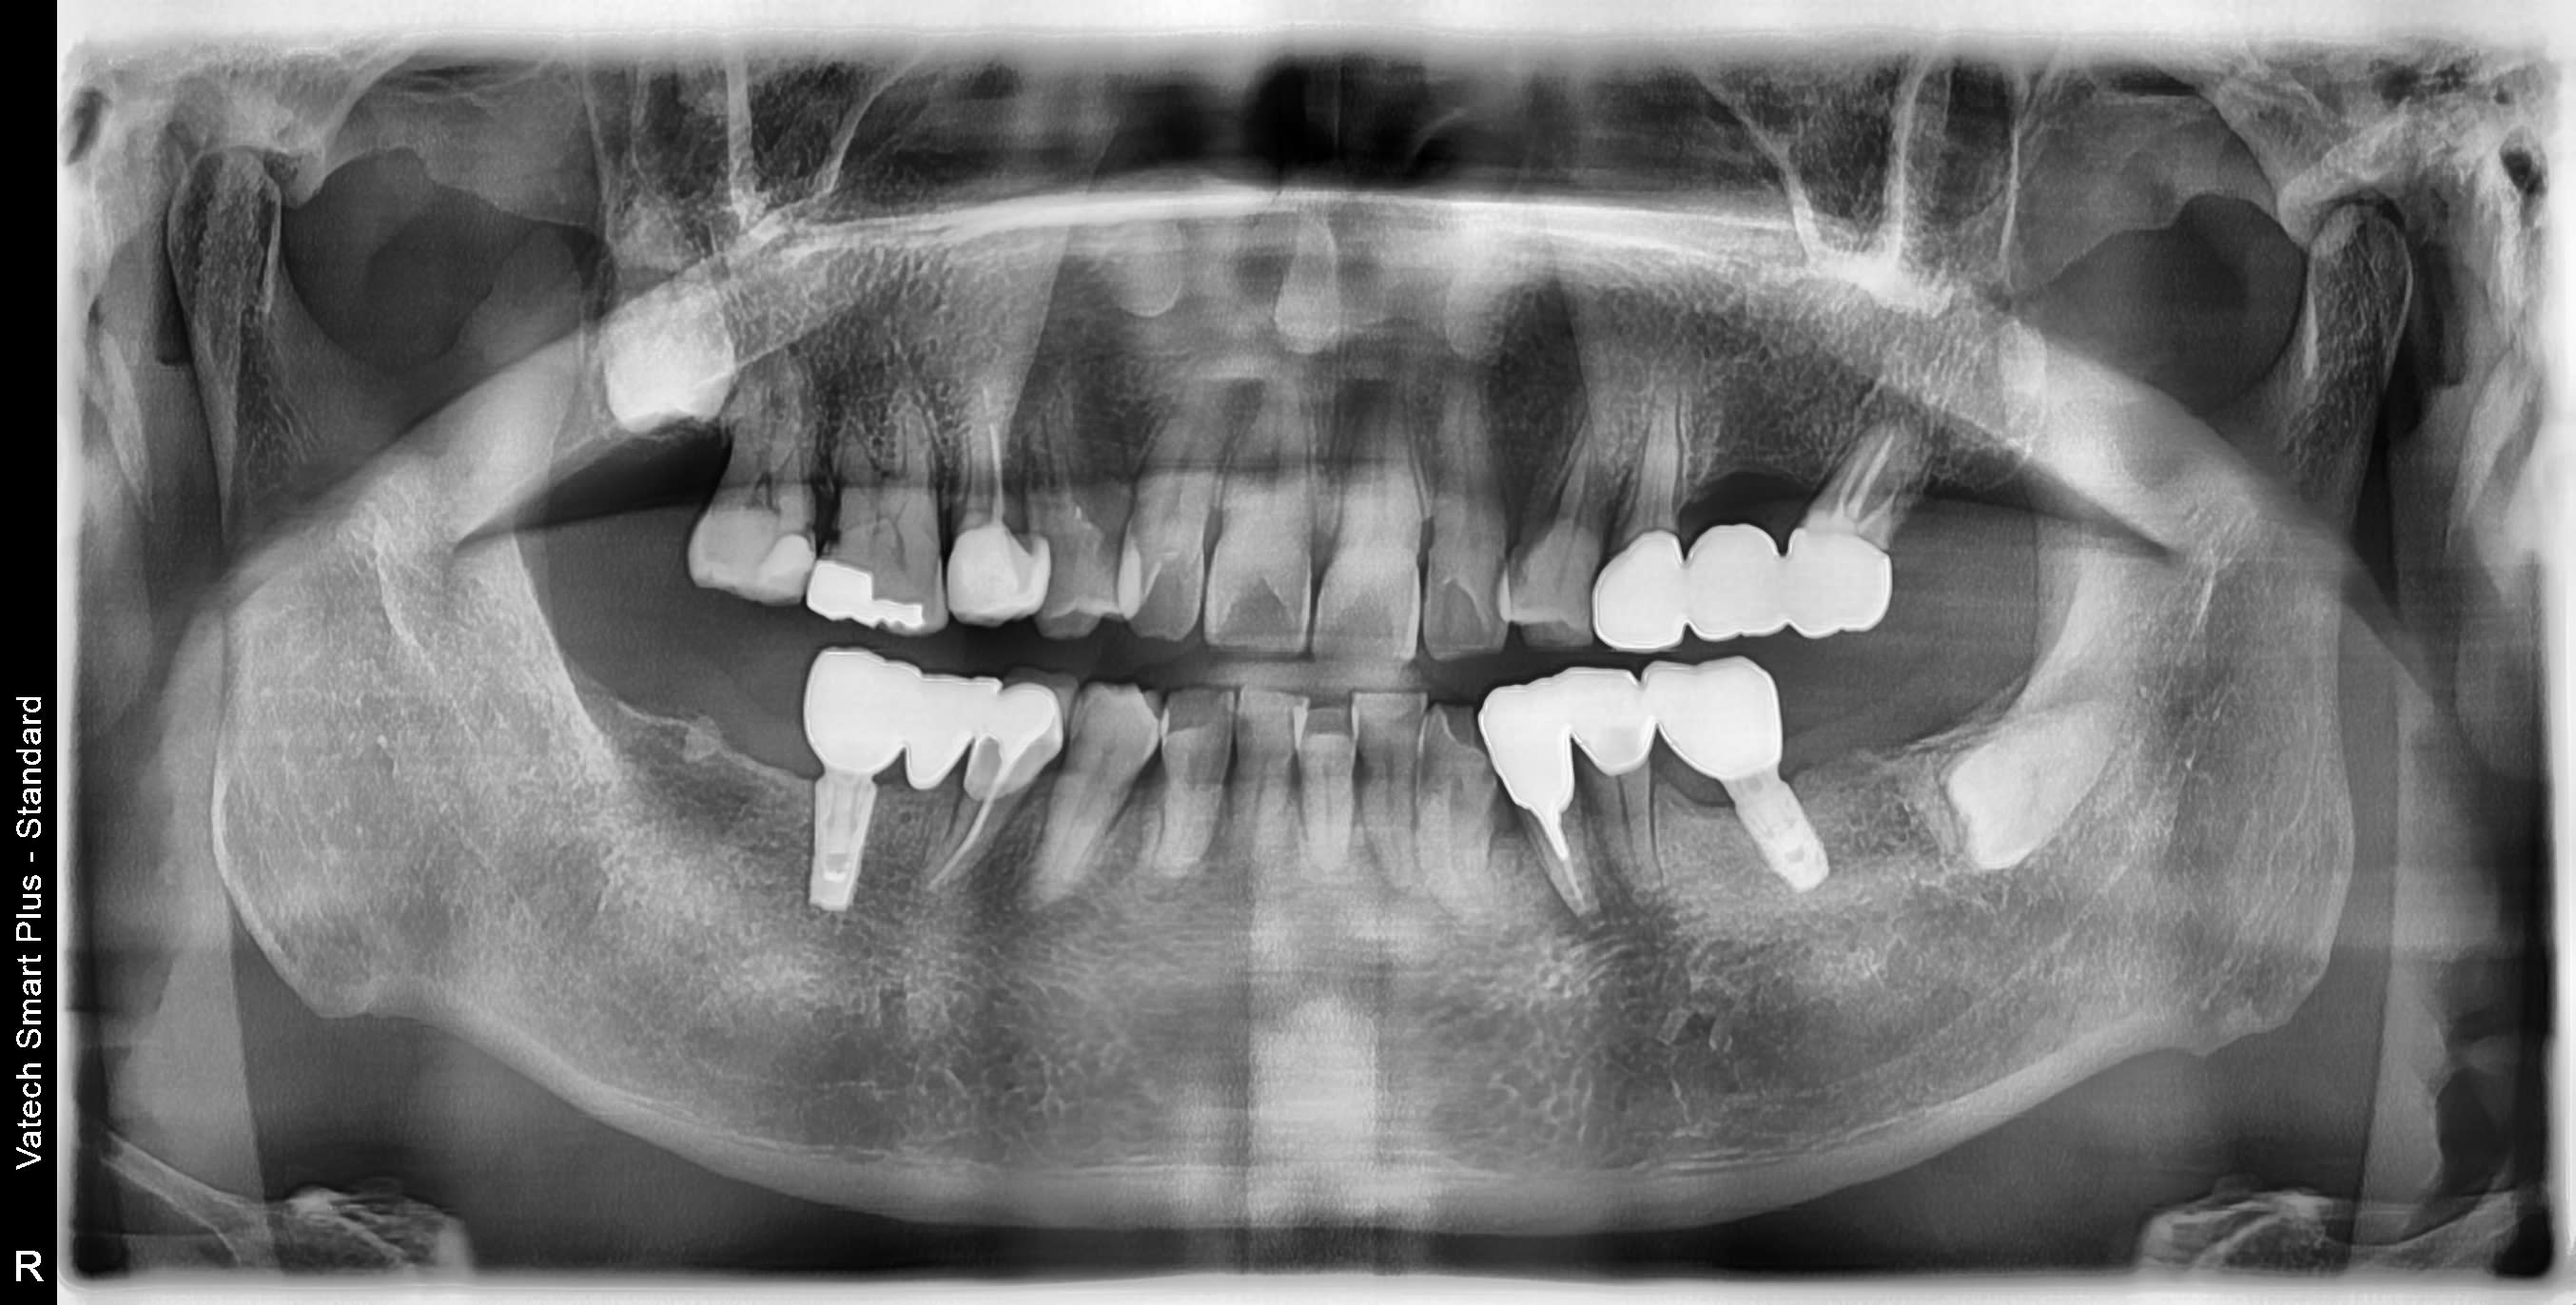

je cherche la marque de l'implant en 46 svp.

Posé au Japon il y a 5 ans environ

De repos, et il veut une bonne retro alvéolaire comme d’hab, parce que le zoom de la pano on voit rien, …..